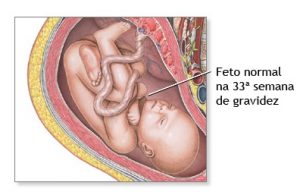

33 semanas de gravidez

33 Semanas de Gestação

Sua 33a semana começa

- Desenvolvimento o bebê está todo formado e ganhando peso, agora o foco é o amadurecimento dos pulmões.

Com 33 semanas de gravidez, a voz da mamãe e seus batimentos cardíacos são os sons mais agradáveis do mundo para o bebê! Com cerca de 43,7 centímetros e algo em torno de 1,918 kg, ele chuta e pode até mesmo se virar para a posição cefálica , de cabeça para baixo e pronto para o nascimento1. Mas tem alguns bebês que gostam é de ficar sentados na barriga da mamãe e, nesses casos, se não houver mudança até o nascimento o médico pode recomendar uma manobra manual ou optar pela cesárea.

Desenvolvimento do Bebê

Na 33 semana de gestação, o sistema auditivo já está completamente formado2 e o bebê consegue reconhecer nitidamente o som da voz da mamãe, do papai e de familiares próximos, bem como responder com chutes e movimentos se estimulado. Chutes que podem, inclusive, atrapalhar bastante a qualidade do sono da mamãe, já que costumam ocorrer até mesmo durante as madrugadas.

Cada osso do seu corpinho já está rígido, exceto o crânio que ainda não se fundiu para facilitar o momento do parto. As partes da cabeça se encaixam como um quebra cabeça durante a passagem pela pelve materna, sabia? A natureza humana é perfeita! Tudo se forma, se desenvolve e se aperfeiçoa na hora certa. Se está na 33 semana de gravidez e grávida de gêmeos fique alerta, o dia do nascimento pode estar bem próximo!

A quantidade de líquido amniótico que envolve o bebê está diminuindo e chegando ao seu limite3. Isso é sinal que o fim está chegando e que o dia de conhecer seu maior tesouro está se aproximando!! Com 33 semanas, falta muito pouco para seu bebezinho estar em seus braços!!